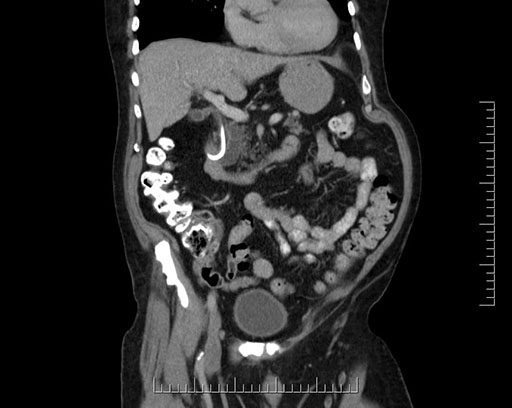

Imaging Analysis

Look through the patient's CT scan to identify any areas of concern for the necessary procedure.

Based on your CT findings, which issue(s) would give reason for "planned slowing down moment(s)" in this case?

Considering a standard Whipple procedure, what step(s) of the operation would you do differently in this case?